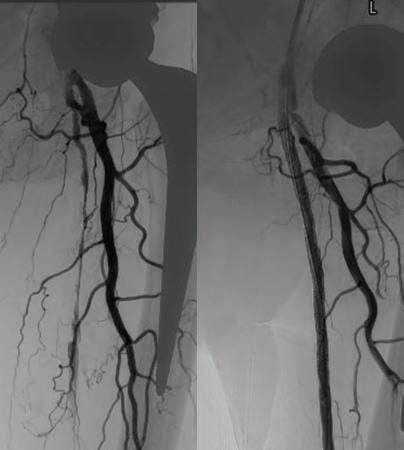

In 2023, there was a 9% increase in cases of Syphilis < 2 years of duration in Australia. This increase is of concern, as a baby can contract congenital syphilis through transplacental transmission. The transmission rate is highest (60-90%) during untreated primary and secondary syphilis.

Testing during pregnancy: Offer routine syphilis testing at the first antenatal visit. Recommend follow-up testing at 28–32 weeks, dependent on local guidelines.